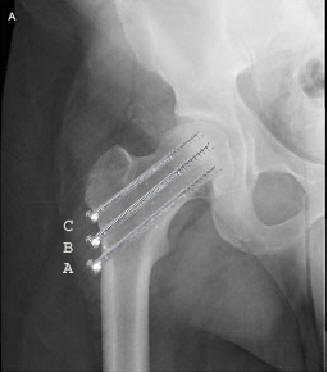

• Intern fiksation med 3 parallelle kannulerede skruer, eller med 2 huls

glideskrue

Ved anvendelse af skruer er der følgende krav:

• At den distale skrue hviler på calcar

• At afstanden fra skruespidsen til den subchondrale knogle skal være ca 5mm

• At der, i fald der indsættes 3 skruer eller flere, skal tilstræbes spredning

af skruerne i sideplanet

• At undgå rotation af caput i forbindelse med isætning af skruer

• At undgå penetration af caput med boret

3 Kannulerede skruer (ved fraktur i det skraverede område) Se skrue

placering på billede A og B: